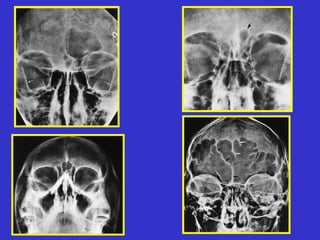

Este documento describe las diferentes proyecciones radiográficas utilizadas para examinar los senos paranasales, incluyendo las proyecciones básicas de Caldwell, Waters lateral y las proyecciones especiales como Hirtz y Waters mentonasal. También describe las diferentes estructuras anatómicas que componen el complejo ostiomeatal anterior y posterior de los senos paranasales.